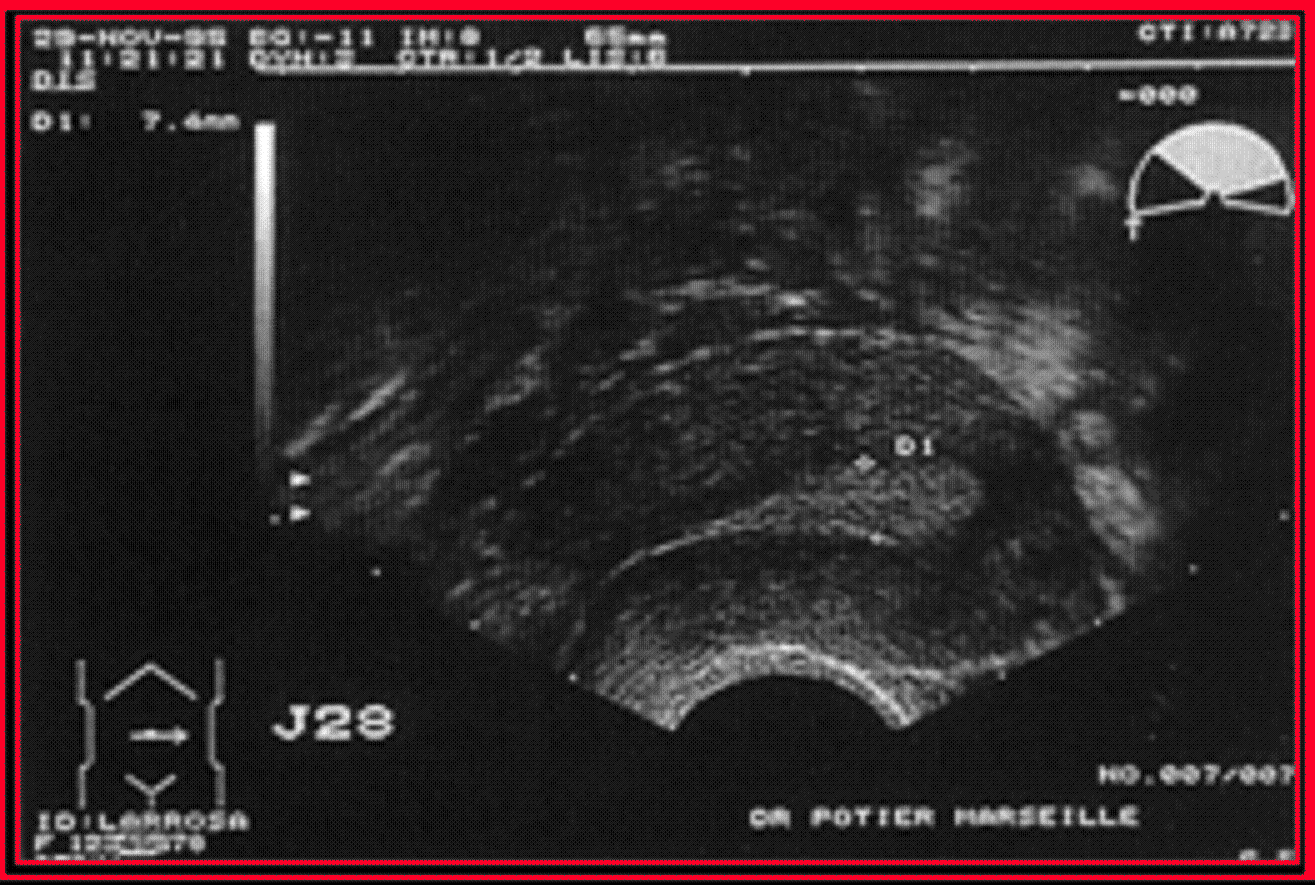

L'échographie reste indispensable lors d'une stimulation ovarienne et, en cas de FIVETE, pour la surveillance de la croissance folliculaire et la ponction des follicules mûrs : on utilise alors une sonde vaginale.

L'utérus est également bien vu en échographie, l'endomètre se distinguant nettement du myomètre.

L'échographie est le premier examen à proposer dans l'évaluation des malformations de l'appareil génital féminin :

- L'échographie est l'examen de référence dans le diagnostic des fibromes dont elle permet d'établir une cartographie précise,

- L'échographie est moins performante pour le diagnostic d'adénomyose.

- L'injection d'un liquide dans la cavité utérine constitue l'hystérosonographieDéfinitionExamen d'échographie permettant l'étude des parois de l'utérus, de la cavité de l'utérus, et de la partie proximale des trompes utérines. Il consiste à introduire, dans le col de l'utérus, un cathéter, servant à injecter du sérum physiologique, et à pratiquer l'échographie pendant l'injection du sérum physiologique. Cet examen, actuellement très utilisé en gynécologie, a remplacé l'hystérographie dans beaucoup de ses indications. C'est un examen indolore, sans risque allergique, mais qui reste contre-indiqué en cas de grossesse. et améliore les performances de l'échographie dans l'évaluation des pathologies intra-cavitaires.